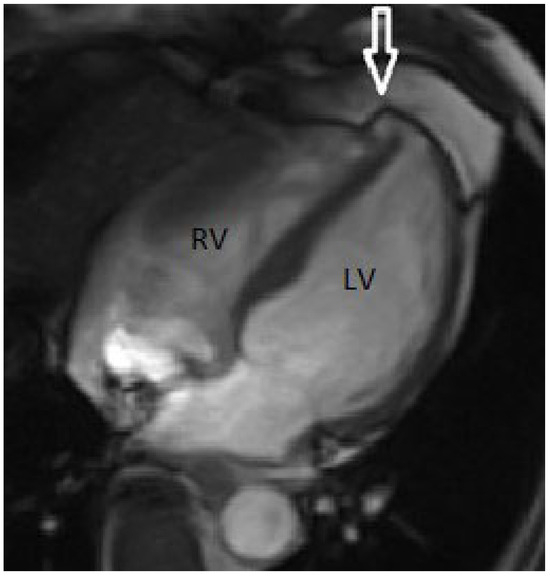

Congenital Left Ventricular Diverticulum in an Asymptomatic Patient: Multi-Modal Evaluation

by Negro Alessandro, Carballo David, Noble Stéphane and Müller Hajo

Congenital left ventricular diverticula are rare cardiac malformations. Few data are available regarding their prevalence, which is estimated to be around 0.04% and 0.7%, according to retrospective series. In our case a diverticular apical lesion of the left ventricle was incidentally found on [...] Read more.

Congenital left ventricular diverticula are rare cardiac malformations. Few data are available regarding their prevalence, which is estimated to be around 0.04% and 0.7%, according to retrospective series. In our case a diverticular apical lesion of the left ventricle was incidentally found on an urgent thoracic computed tomography scan, performed to rule out abdominal aortic rupture. A thorough evaluation with echocardiography, coronary angiography, ventriculography and cardiac magnetic resonance imaging was performed. After discussion in our heart team, which took into consideration the lack of cardiac symptoms, the small size of the diverticulum and the absence of thrombus, we decided on a conservative option. Full article